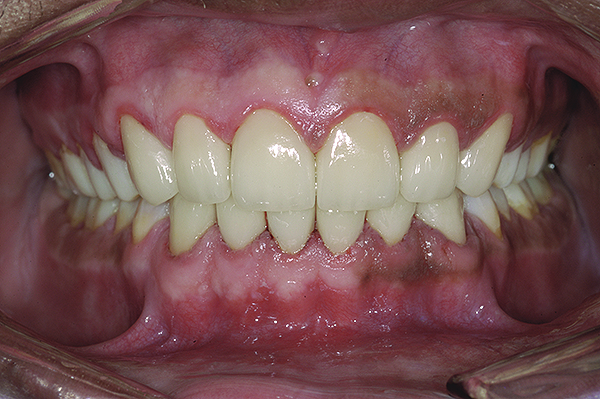

Figure 23. Postoperative 1:1 retracted frontal view.

Figure 23

The final restorations depicted restoration of form, function, and beauty, with good harmony of restoration and the periodontium (Figure 19 through Figure 25). MIP was in harmony with CR, and right and left lateral excursion discluded all posteriors with anterior group function. The postoperative orthopantomogram (OPG) (Figure 26) shows the treatment done while maintaining the vitality of anterior teeth.